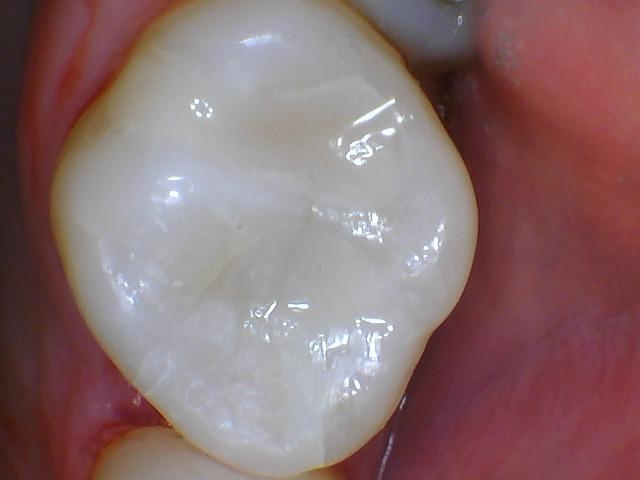

This old silver filling had been in place for many years and was beginning to show signs of failure.  The gray discolorization around the filling is a sign of a leaking and failing filling.  As a filling begins to break down, moisture begins to be let in around the filling.  As moisture and bacteria begin to invade the tooth around the filling, tooth decay soon follows.  This filling was removed and replaced with tooth colored resin filling material.  One of the main advantages of tooth colored filling material is the superior esthetics.  We can eliminate the dark colors of the decay and metal fillings and replace them with a material that is much more natural in appearance.